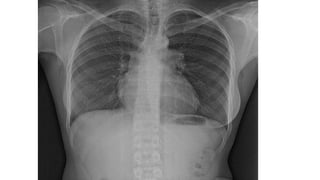

• Radiographie thoracique

• Télécoeur (Radiographie thoracique)